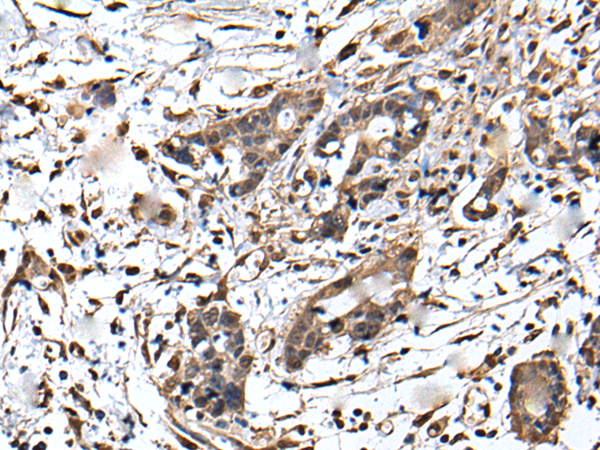

IHC positive control: |

Human brain and human gastric cancer |

IHC Recommend dilution: |

40-200 |